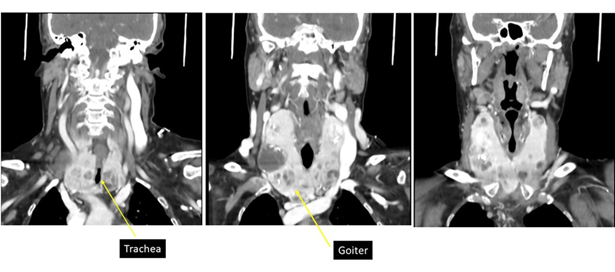

The ct of the neck reported: multinodular goiter with intrathoracic extension from the operculum 19 mm, volume 71 cc. Visceral axis of the neck well centered. No alterations are observed in the walls of the pharynx. Fatty spaces for pharyngeal muscles preserved

(figure 6).

Figure 6: ct with goiter that maintains undamaged tracheal lumen.